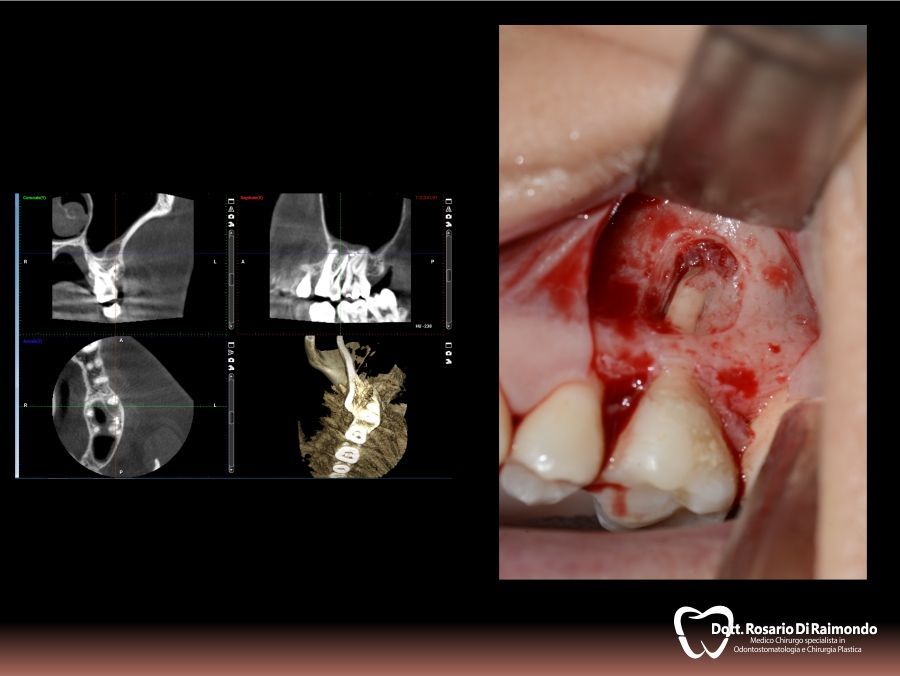

Apicectomie

L'apicectomia è un piccolo intervento chirurgico rivolto a rimuovere il granuloma apicale nei denti malati in cui la terapia canalare tradizionale non prospetta un risultato predicibile.

In molti casi, la rimozione del granuloma dentale si associa alla asportazione dell'apice radicolare.

L'indicazione più frequente per l'apicectomia è l'insuccesso di una terapia endodontica di un elemento dentario la cui conservazione è ritenuta necessaria.

Casi Trattati

Di seguito riportiamo alcune fotografie di casi esplicativi di Chirurgia Orale.